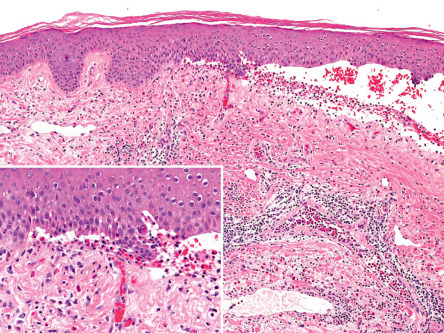

In the non-bullous phase or in atypical variants of BP, routine histology may provide less specific information, since only eosinophilic spongiosis and/or dermal infiltrates of eosinophils may be seen ( Fig. 30.9 ). In biopsy specimens of an early bulla, a subepidermal blister accompanied by a dermal inflammatory infiltrate composed of eosinophils and mononuclear cells is typically observed. The infiltrate favors the uppermost dermis, and the cavity of the bulla contains a net of fibrin with a variable inflammatory infiltrate ( Fig. 30.10 ). Electron microscopy studies have shown that subepidermal blister formation occurs at the level of the lamina lucida.